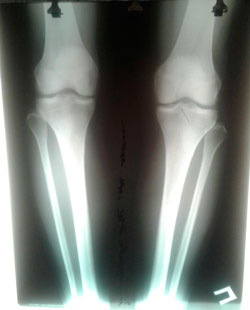

РЕНТГЕН ДО ОПЕРАЦИИ